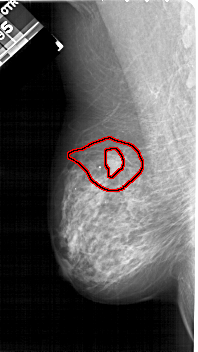

A_1211_1.LEFT_MLO

LEFT_MLO LINES 5266 PIXELS_PER_LINE 2956 BITS_PER_PIXEL 12 RESOLUTION 43.5 OVERLAY

FILE: A_1211_1.LEFT_MLO.OVERLAY

TOTAL_ABNORMALITIES 1

ABNORMALITY 1

LESION_TYPE MASS SHAPE IRREGULAR MARGINS SPICULATED

ASSESSMENT 5

SUBTLETY 5

PATHOLOGY MALIGNANT

TOTAL_OUTLINES 2

BOUNDARY

CORE